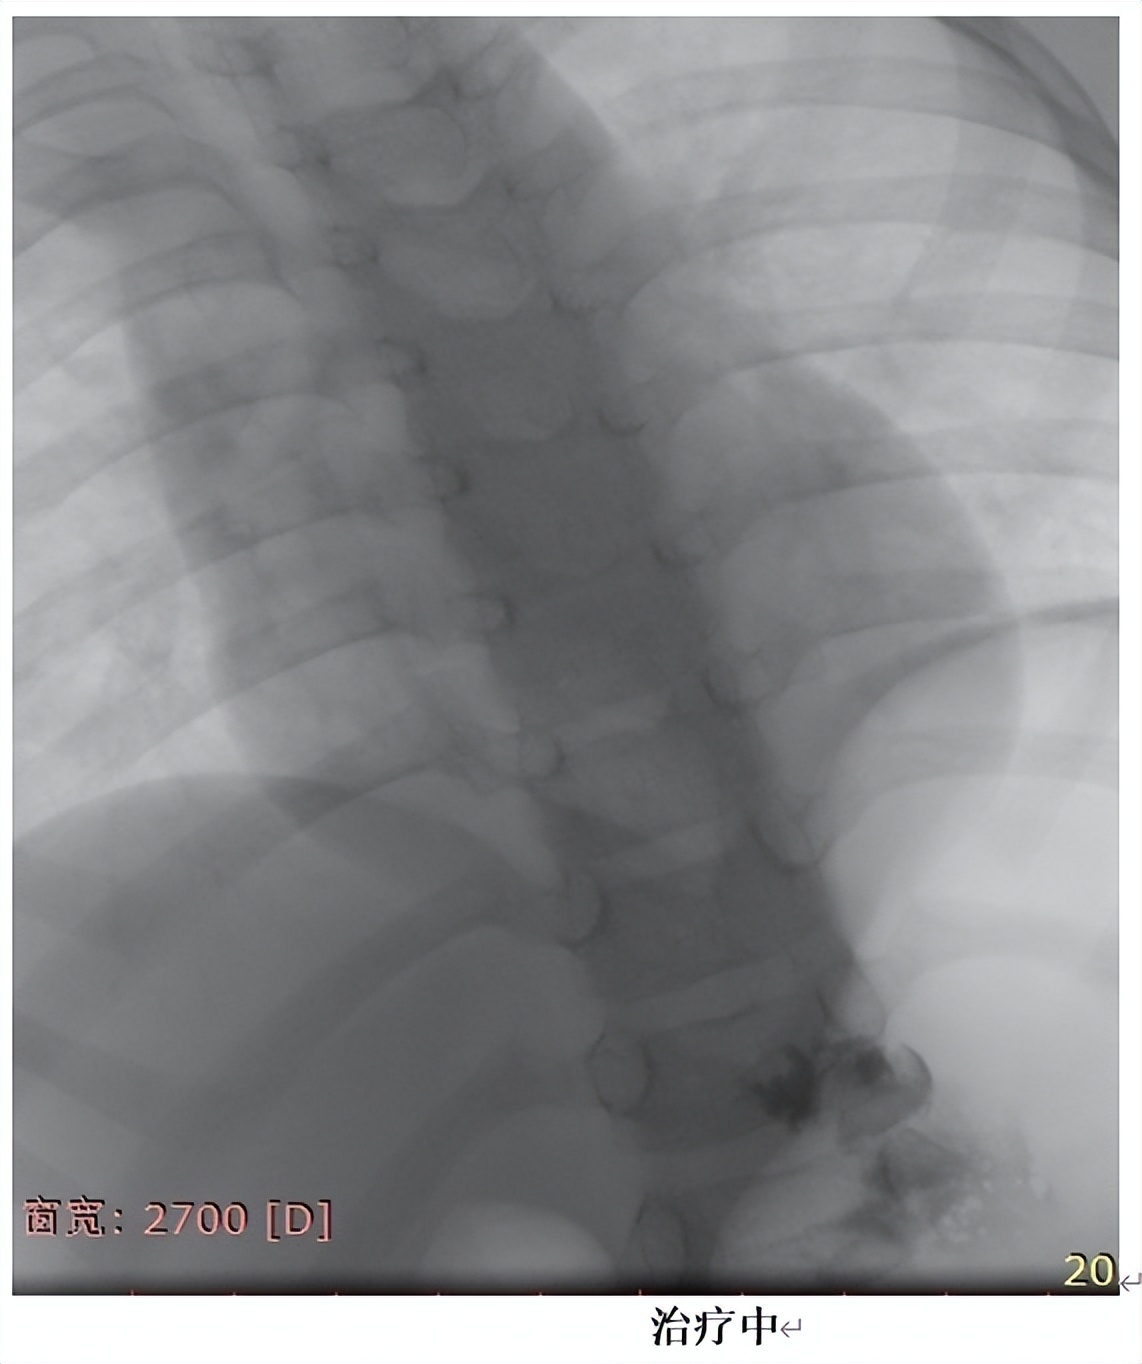

在安排的手术时间,家长如约住院,顺利完成术前准备,手术当天,患儿在全麻的过程中完成了手术,手术仅耗时半小时,术中无出血,手术过程非常顺利,术后孩子也没有任何不适,身上也没有任何伤疤。共住院3天,患儿平稳出院。

接着,患儿又进行两次的介入治疗,肿物逐渐缩小,本患儿为巨大腹壁淋巴管瘤患儿,共介入治疗3次,患儿病灶基本完全恢复正常。微创、无痛、不遗留伤疤、花费小,推荐介入治疗为淋巴管瘤患儿的一线治疗方案。家长满意度高,我们也由衷地替患儿开心!